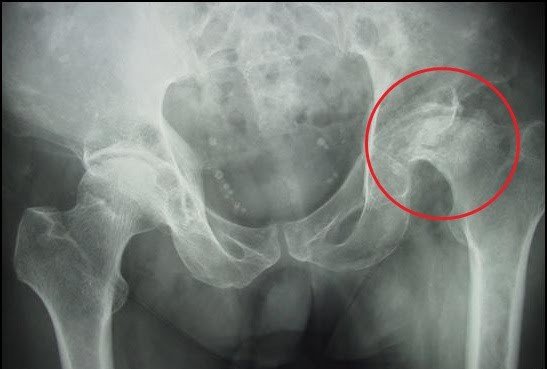

Hình ảnh: Hoại tử chỏm xương đùi

- X quang: Bao gồm phim chụp X quang khớp háng thẳng và nghiêng, xquang khớp háng kiểu đùi chếch là phương tiện đầu tiên được lựa chọn để chẩn đoán hoại tử chỏm xương đùi.

Hình ảnh: Nhẹ thấy hình ảnh xương thưa, thường thấy xẹp chỏm từ nhẹ đến nặng, nặng nhất là thấy mất một phần hoặc hoàn toàn chỏm, hình ảnh hẹp khe khớp.

Hình ảnh hoại tử chỏm xương đùi qua phim chụp Xquang